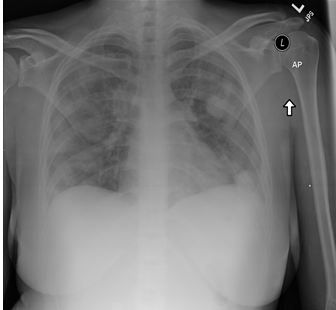

Fig 1. Chest x-ray shows cavitary lesions in both lung fields.

Laboratory evaluation showed WBC of 28,000/cm3 with left shift and thrombocytopenia. Results of rapid strep and mono spot tests were negative and blood cultures were drawn. Initial chest x-ray showed multifocal nodular infiltrates suspicious for septic emboli (Figure 1, click to enlarge). She was admitted to ICU for presumed sepsis and was treated with vancomycin and piperacillin-sulbactam (Zosyn).